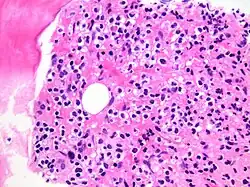

This occurs when immune cells like lymphocytes and macrophages migrate into tissues in response to infection, injury, or inflammation, aiding in defense and healing but potentially contributing to autoimmune diseases if misdirected.[1] Immune cells (especially lymphocytes) also infiltrate into malignant tumors and other neoplasms.[2]

Hairy cell leukemia infiltrating bone marrow, an example of malignant infiltration

Malignant infiltration involves cancerous cells invading surrounding healthy tissues by breaching normal cellular boundaries, which allows tumors to grow locally and facilitates metastasis to distant organs. This is especially relevant for cancers that cross the blood-brain barrier and cause secondary brain tumors.[3]